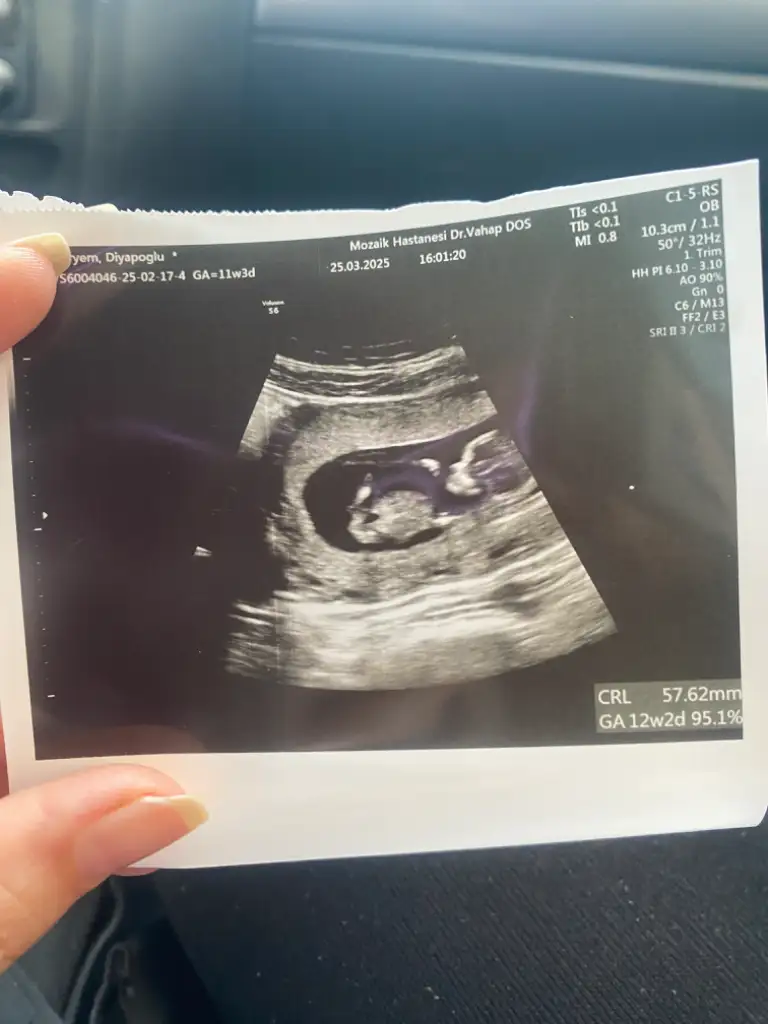

Kızlar 12 haftalık gebeyim. Nub teorisine göre cinsiyet tahmini yapabilir misiniz? İlk bebeğimiz ve biz cinsiyeti çok merak ediyoruz

Eklentiler

• IMG_5708.webp

28 KB · Görüntüleme: 798